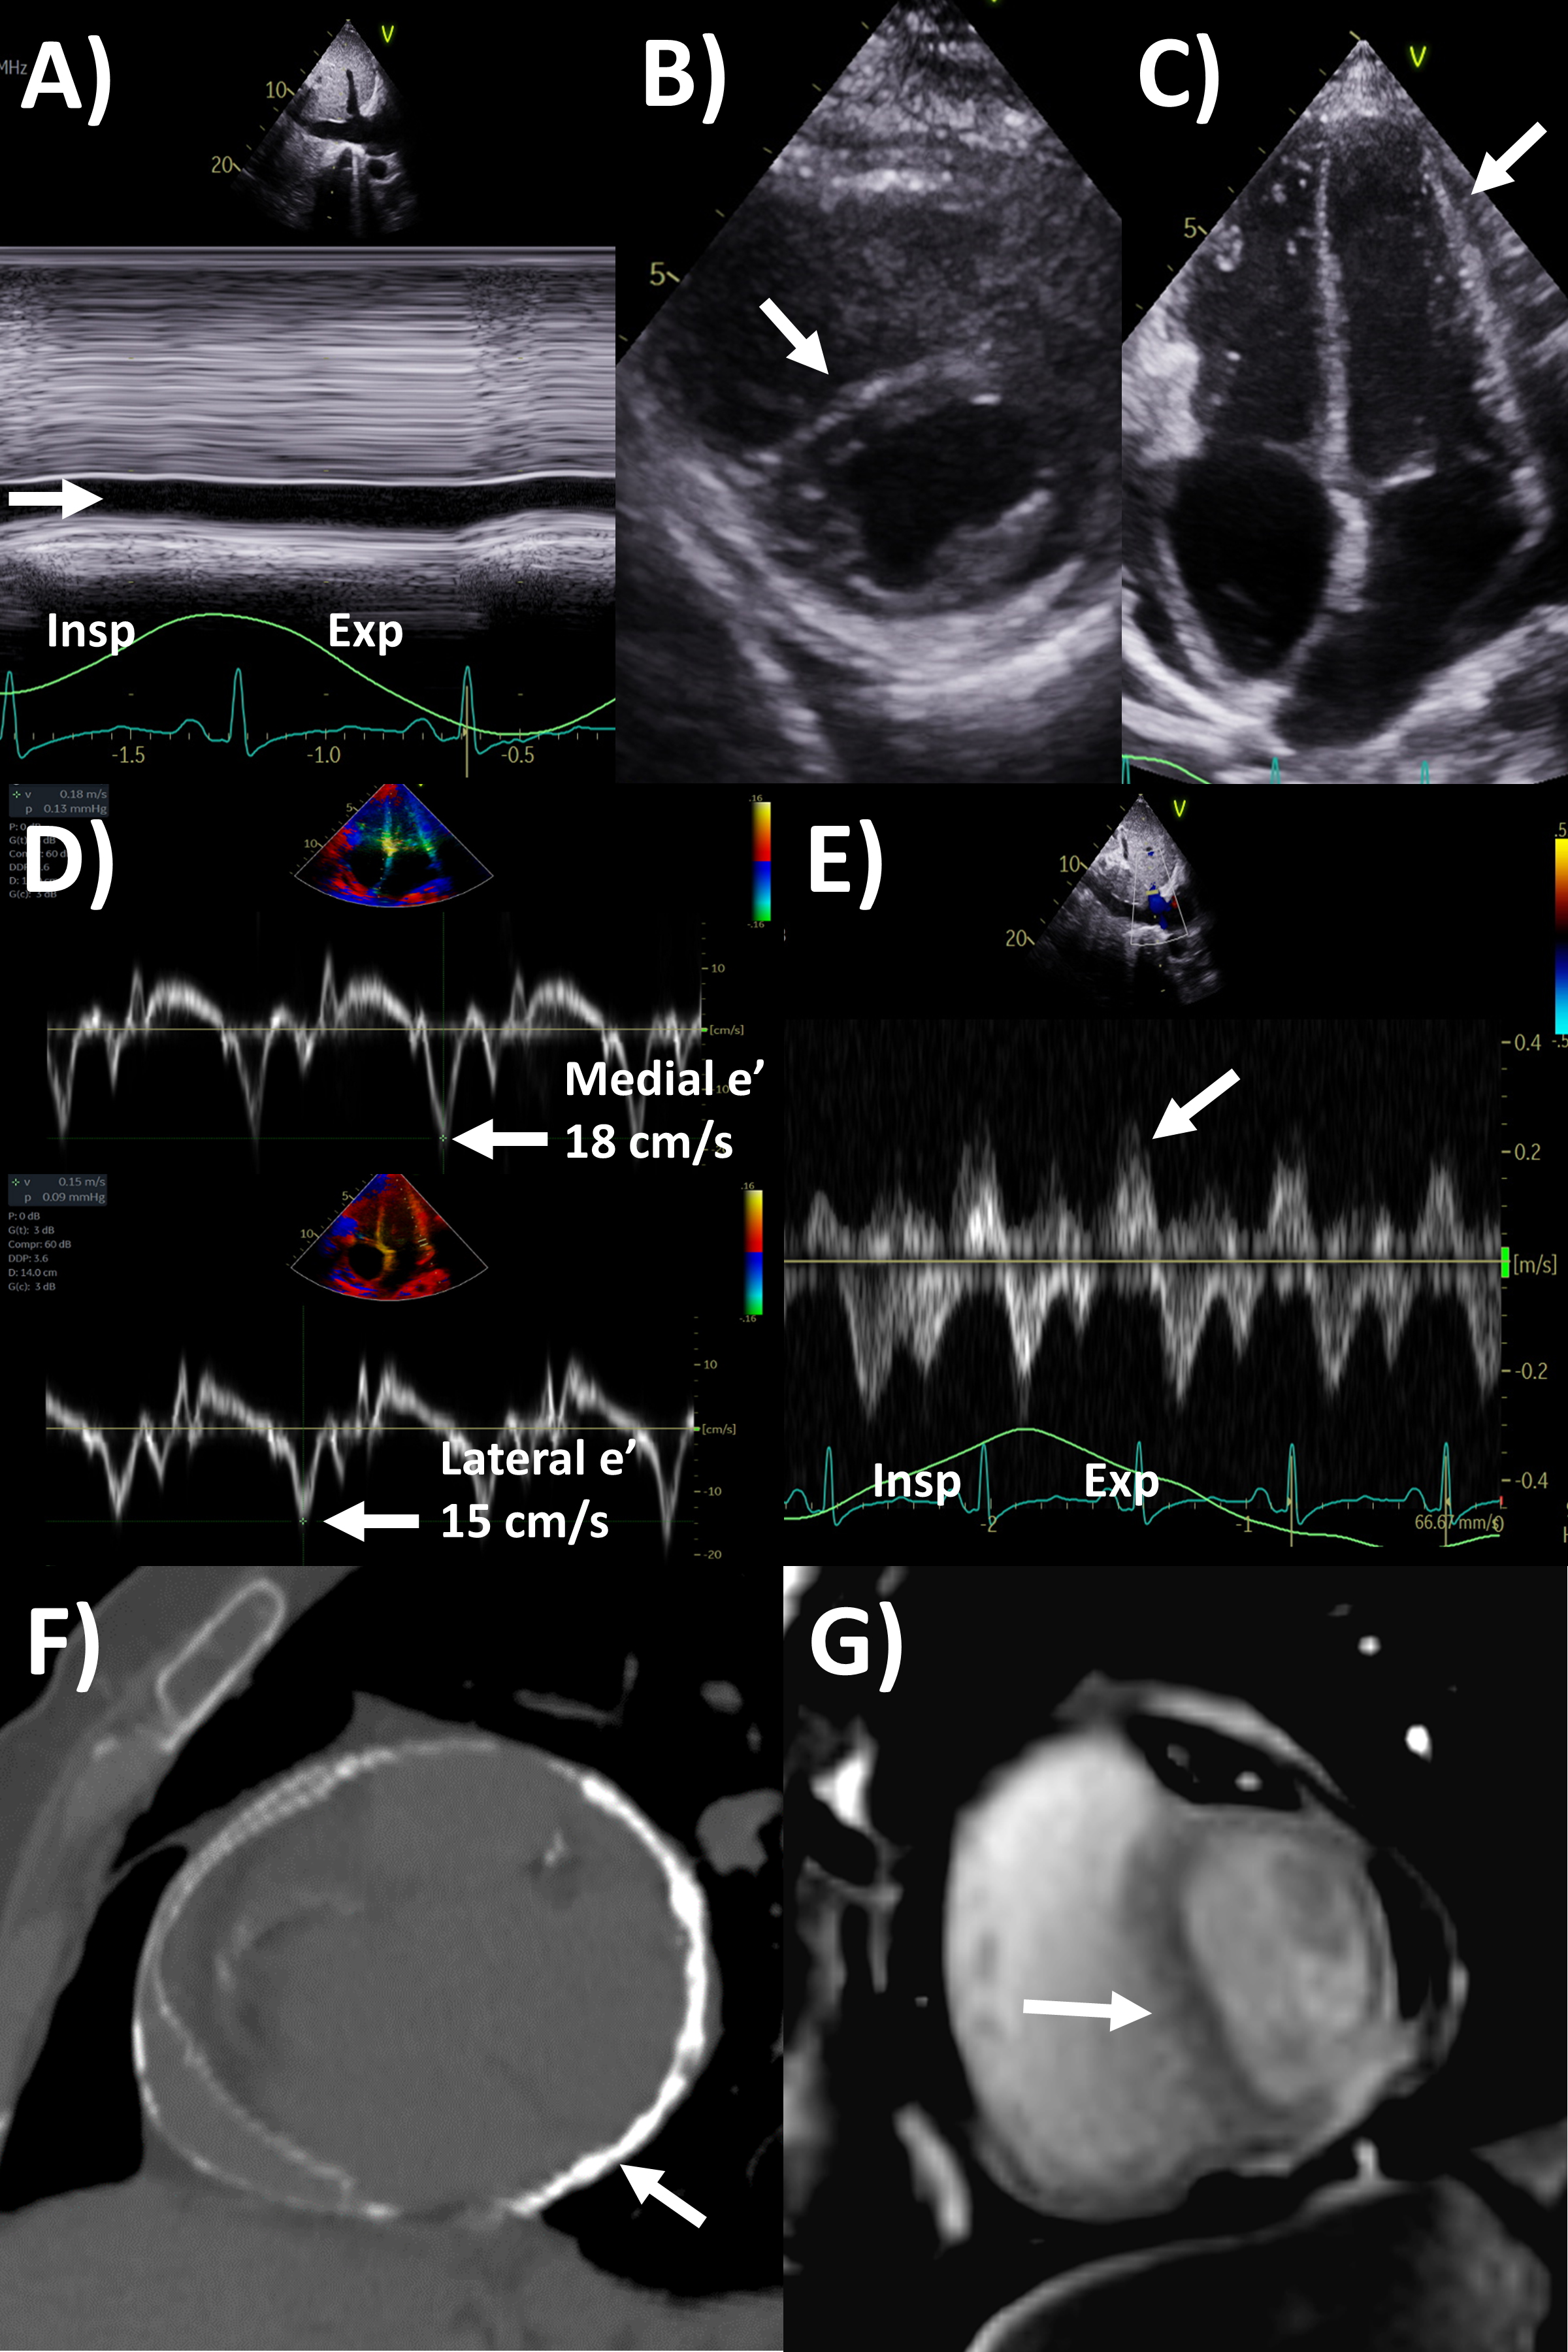

echocardiographic criteria according to guidelines (Fig. 2) include dilated

Fig. 2.Echocardiography evaluation of pericardial tamponade. (A)

Dilated inferior vena cava (2.7 cm) with minimal

Pericardial constriction is a feared chronic complication of pericardial

same etiology but often challenging to diagnose [1, 35]. Echocardiography is also

the first-line and often self-sufficient modality for evaluation of constrictive

physiology [2, 36]. The Mayo Clinic Criteria being the recommended algorithm for

restriction or diastolic dysfunction, with several key findings shown in (Fig. 3)

[36, 37, 38]. The first part of the algorithm has the dual criteria of mitral inflow

E/A ratio

Fig. 3.Multi-modality imaging evaluation of constrictive pericarditis.

Echocardiography (A) dilated inferior vena cava (2.3 cm) with minimal

Of note, in the Mayo Clinic Criteria derivation study, the presence of

respirophasic ventricular septal shift and either medial e’ velocity

MRI is actually a valuable second-line but under-utilized imaging tool for

evaluating constrictive pericarditis [2]. Standard cine imaging with steady state

free precession or gradient echo sequences not only assess chamber size and

function, but also typical constriction findings such as abnormal

interventricular septal motion, wall tethering, conical ventricular deformities,

and dilated inferior vena cava, while free breathing sequences allows assessment

for respirophasic septal shift (Fig. 3) [2, 50]. Pericardial thickness often

increased in constrictive pericarditis can be assessed by these bright-blood

sequences or black-blood spin echo sequences, as well as dilated inferior vena

cava. Quantitative measures include lower short-axis cardiac area at

end-inspiration/end-expiration, and higher relative atrial volume index ratio

(left versus right) to be present in constrictive pericarditis [51, 52].

Acquiring phase-contrast sequences real-time over 10 seconds with free breathing

an detect mitral and tricuspid inflow, with